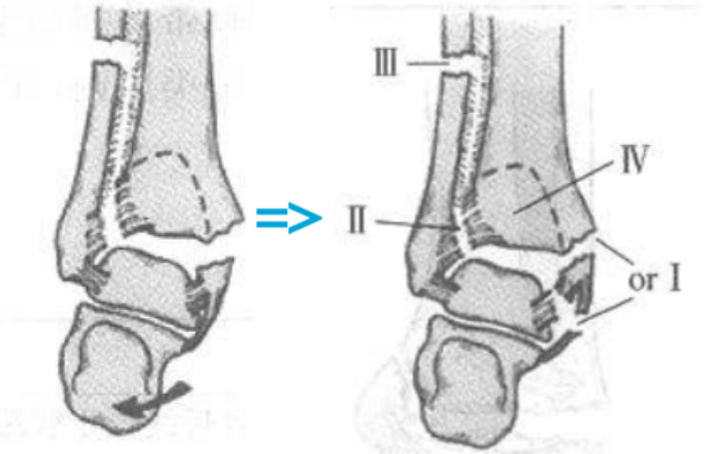

3、旋前(外翻)外旋损伤(简称 PE)

伤足处于旋前位,距骨外旋,三角韧带首先被拉紧。

旋前外旋损伤

I 度:首先发生的是三角韧带的断裂或者内踝的撕脱骨折。

I 度损伤 X 线显示:内踝水平骨折;侧位 X 线片显示后踝完整。这种损伤与旋前外展 I 度非常相似。

Ⅱ 度:距骨外旋力量继续作用于下胫腓关节,下胫腓前韧带和骨间韧带或韧带附着点撕脱骨折。

II 度损伤 X 线显示:内踝间隙增宽,提示三角韧带断裂;胫腓骨间隙增宽,提示下胫腓前联合断裂。

Ⅲ 度:腓骨骨折发生于胫骨远端关节面以上水平,甚至可以位于腓骨近端即 Maisonneuve 骨折,骨折线从前上方斜向后下方,即与旋后(内翻)外旋骨折相反。

III 度损伤 X 线片显示:内踝骨折和腓骨近端螺旋形骨折;胫腓骨间隙增宽;侧位片显示腓骨骨折,后踝无骨折。

Ⅳ 度:最后发生下胫腓后韧带断裂,或其胫骨附着点的撕脱骨折(Volkmann 骨折块)。

IV 度损伤 X 线片显示:内踝骨折;胫腓骨间隙增宽,提示下胫腓联合断裂,腓骨骨折位于下胫腓联合水平上;侧位片显示胫骨向前移位和后踝撕脱骨折。